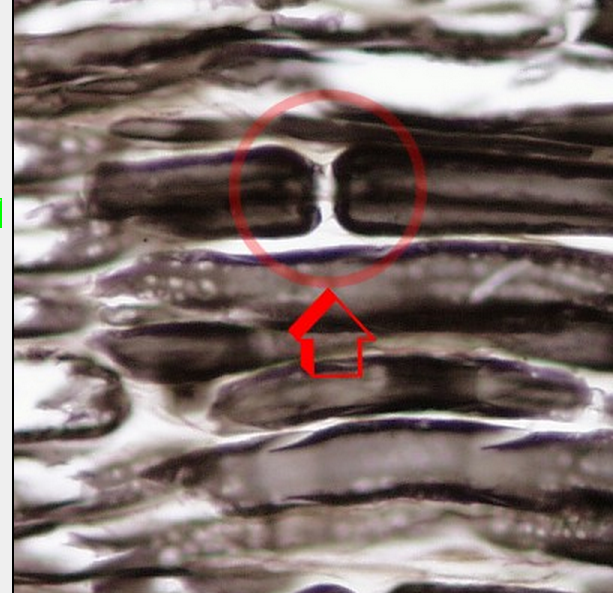

Q

What is the picture indicating?

A

Node of Ranvier (gap in the myeline sheeth)